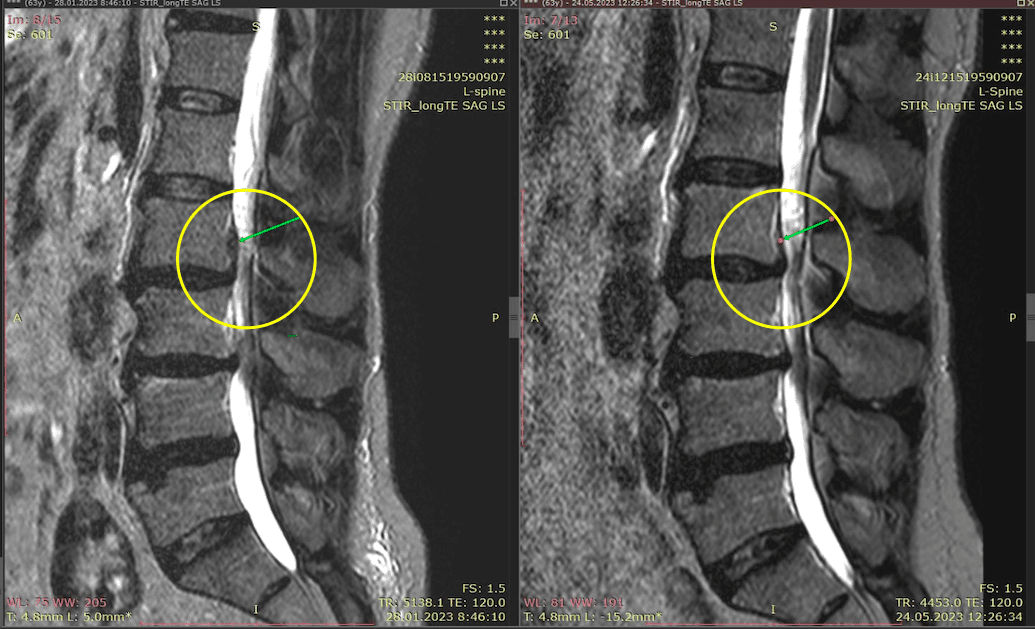

Метод лікування грижі шляхом стимуляції резорбції в Україні був впроваджений у 2020-2021 роках.  Алгоритм оцінки грижі на предмет резорбції, що використовується у клініках – є авторським, розроблений лікарем Боханом А.Ю.